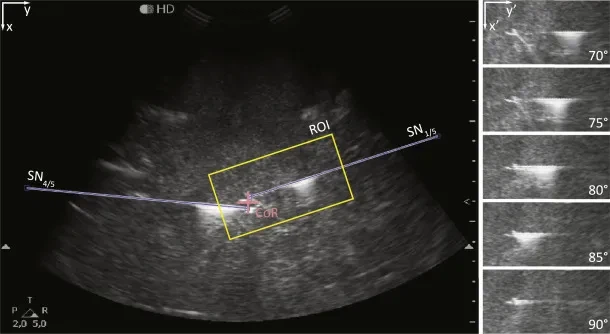

এই যেখানেআল্ট্রাসাউন্ড গাইডেন্সক্লিনিকাল অনুশীলনকে রূপান্তরিত করেছে। অন্ধ কৌশলগুলির বিপরীতে বা কেবল পৃষ্ঠতলের ল্যান্ডমার্ক দ্বারা পরিচালিত, আল্ট্রাসাউন্ড সরবরাহ করেরিয়েল {{0} nar স্নায়ু, জাহাজ এবং আশেপাশের টিস্যুগুলির সময় ভিজ্যুয়ালাইজেশন। অ্যানাস্থেসিওলজিস্ট সুইয়ের ট্র্যাজেক্টোরি ট্র্যাক করতে, স্থানীয় অবেদনিক স্প্রেডকে নিশ্চিত করতে এবং ভাস্কুলার পাঞ্চার বা স্নায়ুর আঘাতের মতো ঝুঁকি হ্রাস করতে পারে।

বাস্তব - সময় সুই ট্র্যাকিং- সুচ টিপের চলাচল অবিচ্ছিন্নভাবে পর্যবেক্ষণ করা যেতে পারে, নির্ভুলতা নিশ্চিত করে।

আসলে, অধ্যয়নগুলি দেখিয়েছে যে আল্ট্রাসাউন্ড গাইডেন্স করতে পারেব্লক সাফল্যের হার 20-30% বৃদ্ধি করুনTraditional তিহ্যবাহী পদ্ধতির তুলনায়, যখন জটিলতার হার উল্লেখযোগ্যভাবে হ্রাস করে। প্রযুক্তিতে এই বিবর্তনটি বিশেষায়িত সরঞ্জামগুলির বিকাশের দিকে পরিচালিত করেছে - বিশেষতইকোজেনিক নার্ভ ব্লক সুইs- যা আল্ট্রাসাউন্ডের অধীনে দৃশ্যমানতা সর্বাধিক করে তোলে।